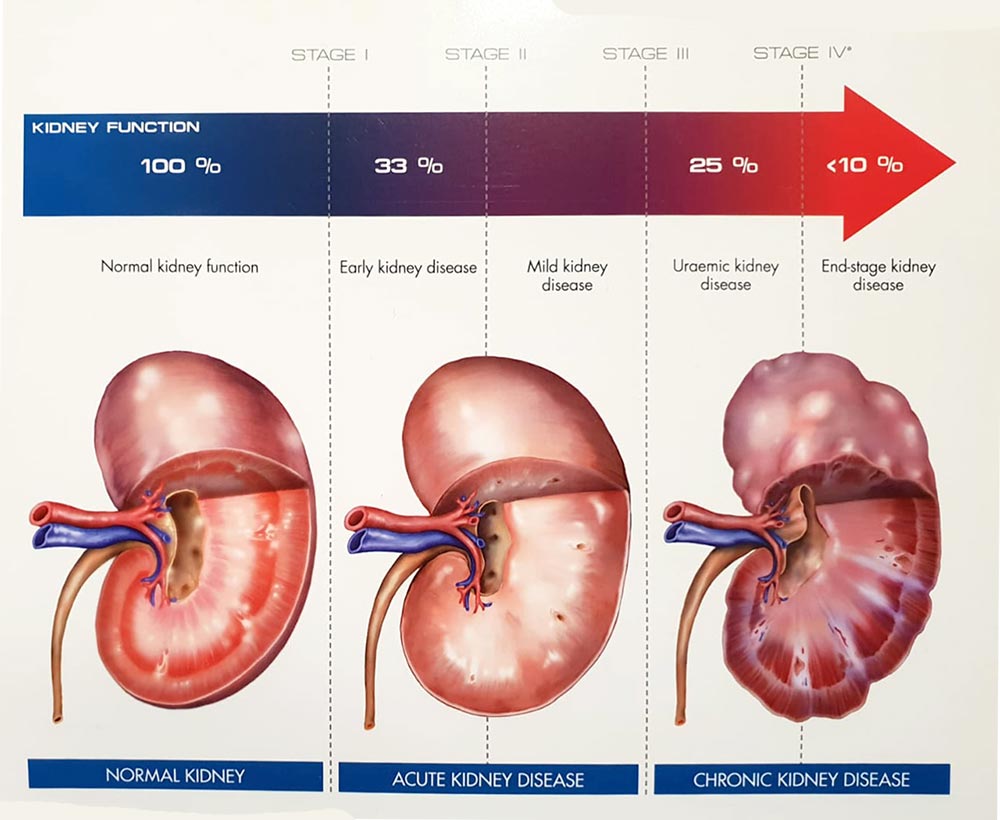

Kidney disease is a common problem affecting about 10% of the world’s population. The kidneys are small but powerful bean-shaped organs that perform many important functions. They are responsible for filtering waste products, releasing hormones that regulate blood pressure, balancing fluids in the body, producing urine, and many other essential tasks. There are various ways in which these vital organs can become damaged. Diabetes and high blood pressure are the most common risk factors for kidney disease. However, obesity, smoking, genetics, gender, and age can also increase the risk. Uncontrolled blood sugar and high blood pressure cause damage to blood vessels in the kidneys, reducing their ability to function optimally.

When the kidneys aren’t working properly, waste builds up in the blood, including waste products from food. Your kidneys filter waste and extra fluid out of your blood so they can be removed from your body in your urine. When your kidneys stop working and can no longer do their job, it’s called kidney failure.

It may even develop into Chronic Kidney Disease, Kidney Damage or Infection, Bladder Damage, and Bladder Stones